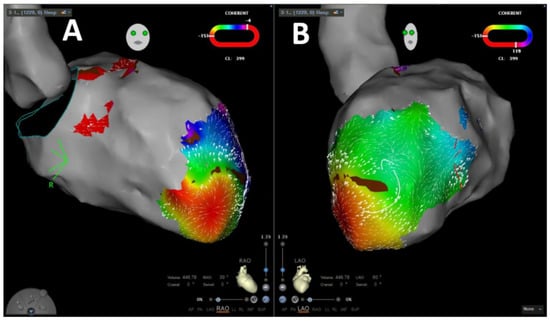

:1. Introduction

2.4. Coherent Mapping

4.1. Velocity Vector Mapping for Guidance of VA Ablation